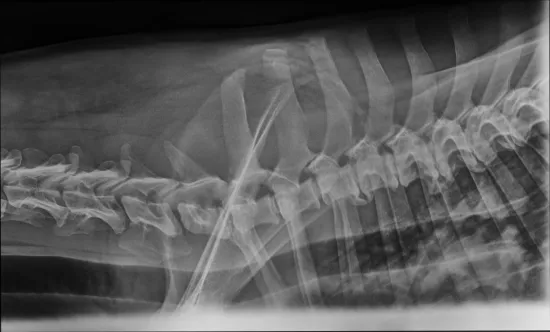

Niedawno trafił do nas starszy pies znaleziony przez pracowników stacji uzdatniania wody. Leżał skulony pod drzewem, cichy, bezbronny, jakby już pogodził się z losem. Kiedy pojechał po niego pracownik schroniska, szybko okazało się, że coś jest bardzo nie tak - pies ledwo się poruszał, z trudem wstawał, każdy krok sprawiał mu ból. Wezwany lekarz weterynarii stwierdził wstępnie zmiany zwyrodnieniowe, podał leki przeciwbólowe i wyraził zgodę na przewiezienie psa do schroniska. Niestety, gdy działanie leków zaczęło ustępować, Magik znów ledwo podnosił się z posłania. Zabraliśmy go do naszego weterynarza na dokładną diagnostykę. Dziś wiemy już więcej. Magik ma około 11 lat, a badania RTG wykazały poważne zmiany w kręgosłupie. Lekarz widzi wskazanie do operacji, ale zanim podejmiemy jakiekolwiek decyzje, konieczne jest specjalistyczne badanie - rezonans, które pokaże, co dokładnie dzieje się z rdzeniem kręgowym i czy operacja ma sens oraz jakie daje rokowania. Takie badanie możemy wykonać tylko w klinice we Wrocławiu. Koszt: 2500 zł. Od tego badania zależy dalszy los Magika. Jeśli okaże się, że można operować - zrobimy wszystko, aby dać mu szansę na życie bez bólu. Na operację uruchomimy osobną zbiórkę.